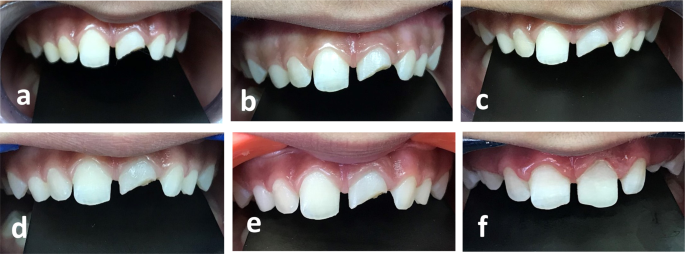

The mean ĪE value at 12 months in the WMTA group was (ĪEā=ā3.64ā±ā2.31) and NeoMTA group was (ĪEā=ā2.99ā±ā2.56). No statistically significant difference between both materials during the 12 months (p value = 0.535). Mean values for ĪE are presented in Fig.Ā 4. Clinical photographs showing the evaluation of discoloration in Group (N) and (W), Figs.Ā 5 and 6.

a Baseline clinical photograph at second appointment, b Clinical photograph at 1 week follow up without discoloration, c Clinical photograph at 1 month follow-up showing shadow of cervical crown discoloration, d Clinical photograph at 3 months follow-up showing cervical crown discoloration, e Clinical photograph at 12 months follow-up showing cervical crown discoloration. f Clinical photograph showing composite buildup.